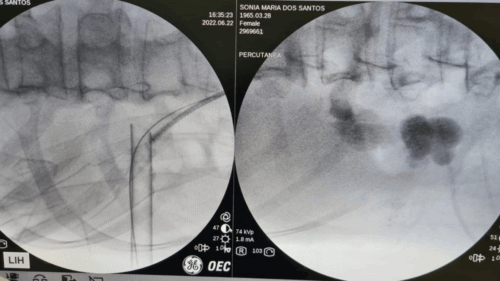

Uma das principais vantagens dessa técnica é a possibilidade de tratar cálculos maiores sem a necessidade de procedimentos mais agressivos, como a nefrolitotripsia percutânea. Segundo o Dr. Carlos, o uso do laser de alta potência reduz o tempo cirúrgico e o risco de complicações, como hipotermia ou necessidade de múltiplas cirurgias.

INDICAÇÕES E LIMITAÇÕES

Essa abordagem pode ser utilizada em praticamente todos os pacientes com cálculos ureterais ou renais. No entanto, existem exceções. Cálculos coraliformes muito extensos, por exemplo, podem exigir cirurgias combinadas, como a nefrolitotripsia percutânea associada à ureteroscopia.

Além disso, condições como infecções urinárias ativas, tumores uroteliais ou alterações anatômicas que dificultam o acesso ao rim pelo ureter podem impedir a realização da técnica — pelo menos temporariamente.